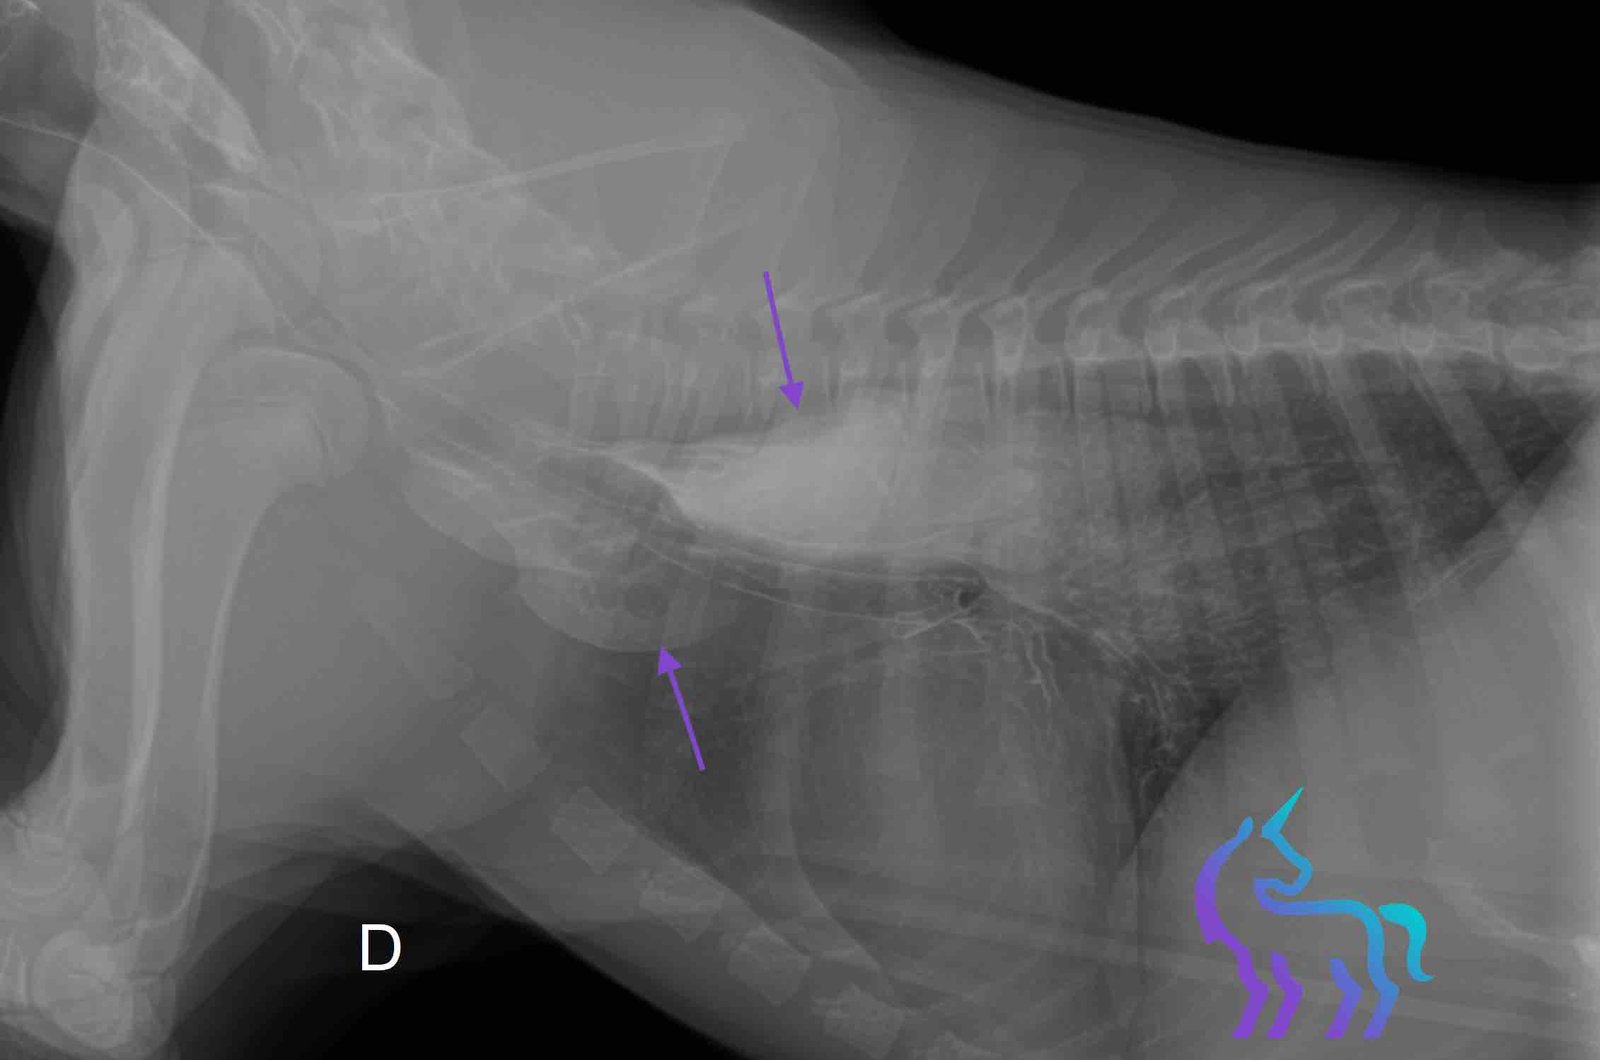

Lésion pulmonaire cavitaire du lobe caudal droit

Espèce : ChienLésion pulmonaire cavitaire du lobe caudal droit, à centre aérique, dans un contexte de morsure récente et de fractures costales associées.

L’hypothèse tumorale a été évoquée puis écartée grâce à l’analyse du contexte clinique et des caractéristiques de l’image.

Diagnostic retenu : Aspect radiographique en faveur d’un abcès pulmonaire.